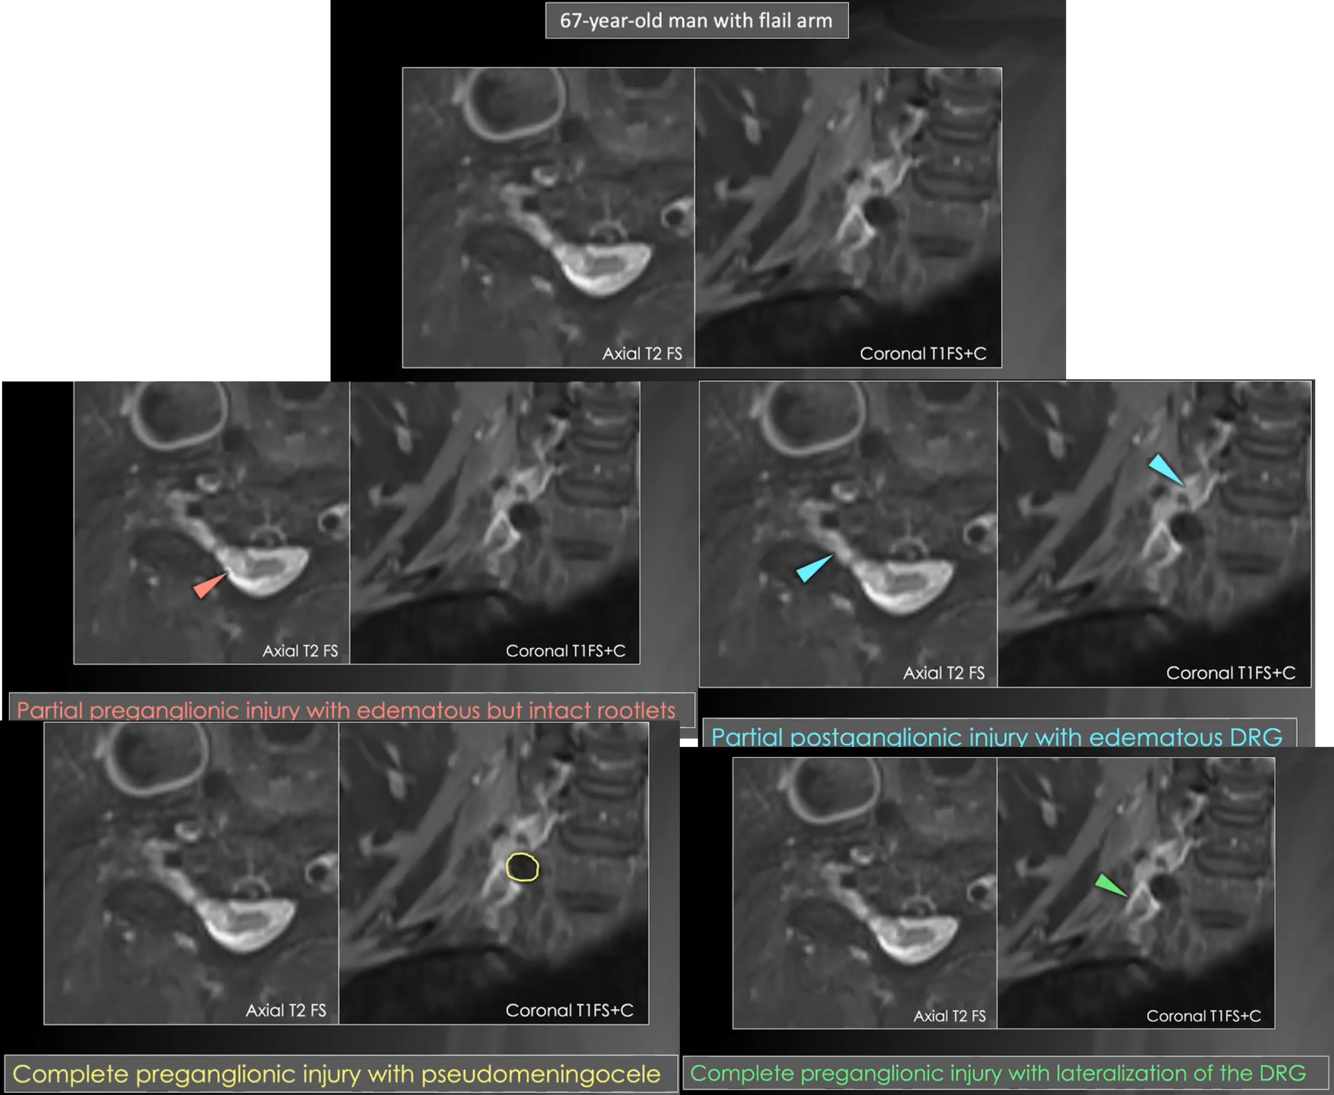

Preganglionic injury

preganglionic injury. discontinuity/absent rootlets, medial to dorsal root ganglion

preganglionic and postganglionic injury in the same case